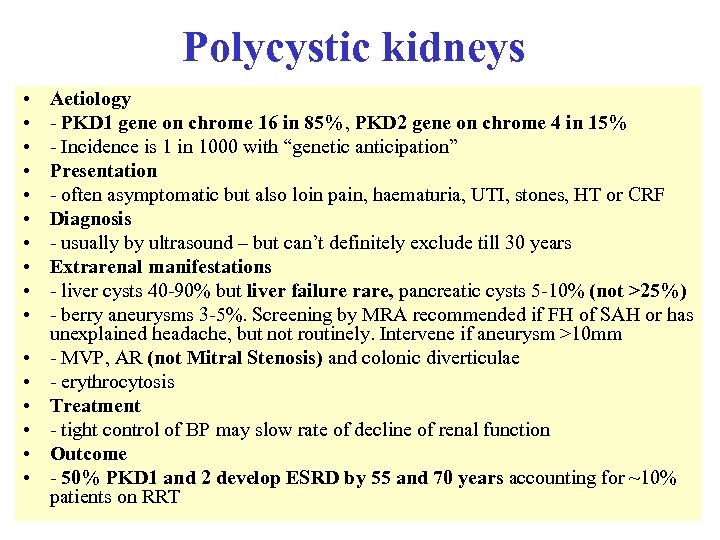

Polycystic kidneys • • • • Aetiology - PKD 1 gene on chrome 16 in 85%, PKD 2 gene on chrome 4 in 15% - Incidence is 1 in 1000 with “genetic anticipation” Presentation - often asymptomatic but also loin pain, haematuria, UTI, stones, HT or CRF Diagnosis - usually by ultrasound – but can’t definitely exclude till 30 years Extrarenal manifestations - liver cysts 40 -90% but liver failure rare, pancreatic cysts 5 -10% (not >25%) - berry aneurysms 3 -5%. Screening by MRA recommended if FH of SAH or has unexplained headache, but not routinely. Intervene if aneurysm >10 mm - MVP, AR (not Mitral Stenosis) and colonic diverticulae - erythrocytosis Treatment - tight control of BP may slow rate of decline of renal function Outcome - 50% PKD 1 and 2 develop ESRD by 55 and 70 years accounting for ~10% patients on RRT

Polycystic kidneys • • • • Aetiology - PKD 1 gene on chrome 16 in 85%, PKD 2 gene on chrome 4 in 15% - Incidence is 1 in 1000 with “genetic anticipation” Presentation - often asymptomatic but also loin pain, haematuria, UTI, stones, HT or CRF Diagnosis - usually by ultrasound – but can’t definitely exclude till 30 years Extrarenal manifestations - liver cysts 40 -90% but liver failure rare, pancreatic cysts 5 -10% (not >25%) - berry aneurysms 3 -5%. Screening by MRA recommended if FH of SAH or has unexplained headache, but not routinely. Intervene if aneurysm >10 mm - MVP, AR (not Mitral Stenosis) and colonic diverticulae - erythrocytosis Treatment - tight control of BP may slow rate of decline of renal function Outcome - 50% PKD 1 and 2 develop ESRD by 55 and 70 years accounting for ~10% patients on RRT